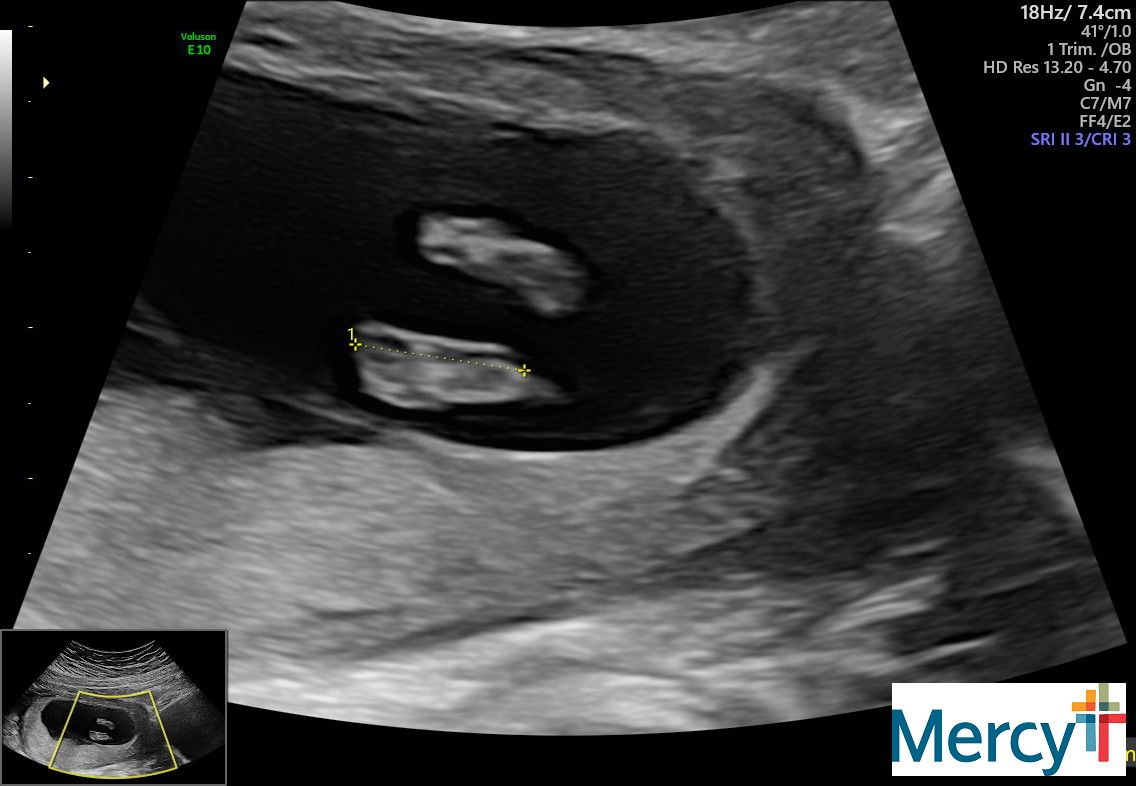

September 9: Back to Dr. Phillips!! 10 weeks

I was extremely nervous for this appointment.. Logan happened to get done with his patient early and was able to come! This was a huge relief for me. I swung down to the school and picked him up and we headed over to Mercy hospital. We went back and got our ultrasound first - and there was the cutest little bean dancing around! It was so crazy and funny to watch, it was fist bumping all around and kicking their legs. It was really great to have Log be there to actually see! We met with Dr. Phillips after, and man I love her! She has been a HUGE support to me, especially when things were really rough. She was thrilled with how things were looking and was very happy for us. We will be back in 3 weeks for another check. :)